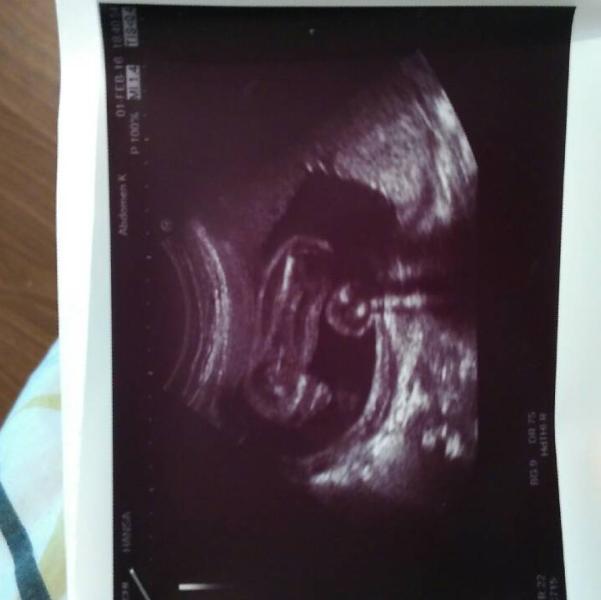

Ходила на узи и дали вот такое фото. С мужем весь вечер голову ломали где что. Может кто то лучше увидит?

Фото видимо послойное... Как я понимаю: фото перевёрнуто у вас в руке, наклоните в лево; там типа тело, нога... А голова осталась в другом слое и УЗИ его не запечатлило.... Ну это мне так кажется конечно